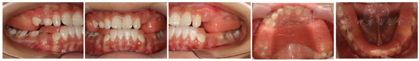

(1)I期治疗:常规取模,以上下颌骨中线齐为标准颌位记录,制作TIPA,其由带较长倾斜平面的上、下颌合垫组成。患者佩戴TIPA,保证矫治器可以在口内充分固位,嘱患者全天戴用,包括进食与睡眠。(图2)前牙反合解除后分次磨低斜导面以利于后牙建合。TIPA戴用12个月后,前牙覆合覆盖正常,凹面型得到改善,观察随访半年显示,治疗效果稳定,面型尚可,进入Ⅱ期矫治(图3)。

(2)Ⅱ期治疗:前磨牙段开合,前磨牙牙根发育2/3,处于萌出建合中。患者及家属选择无托槽隐形矫治(Invisalign,隐适美,墨西哥)进行治疗。设计对齐上下中线,协调双颌宽度,压低内收上下前牙,并对下前牙进行控根移动。为协调上下前牙区Bolton比,在33-43间设计邻面去釉各0.5 mm。该病例隐形方案设计矫治步骤上下颌均为24步。

矫治器佩戴过程中,要求患者除进食、刷牙摘除外,其余时间均需佩戴矫治器,每天戴用至少20小时,每日咬胶不少于4次,每次不少于5分钟,每10~14天自行按序更换下一步矫治器。矫治4个月:矫治器贴合,移动与ClinCheck基本一致(图4)。矫治10个月:矫治器已佩戴完,双侧后牙咬合欠紧密。于双侧后牙(13-16,23-26,34-36,44-46)颊侧龈方粘接舌侧扣,其中上颌6近中粘接舌钮,用3/16英寸(3.5oz)的皮圈行角型牵引,辅助双侧后牙建合(图5)。矫治12个月:前牙建立正常覆合覆盖,后牙咬合尚可。患者对矫治结果满意,要求结束治疗,进入保持阶段(图6)。

总治疗周期30个月,其中TIPA矫治18个月,隐形矫治12个月。矫治后患者侧貌由凹变直;上下牙排列整齐,牙列无间隙,双侧尖磨牙中性关系,前牙覆合覆盖正常,上下牙弓形态位置关系协调,咬合稳定无干扰(图6)。